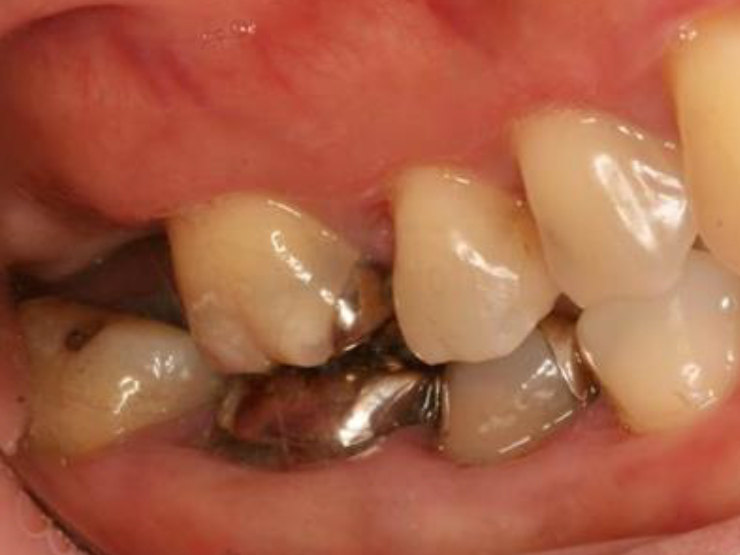

歯周基本治療・根管治療・歯周外科処置を行なった症例

初診時

歯周基本治療・

根管治療後

歯周外科処置

歯周外科処置後

初診時年齢:

治療:歯周病治療・う蝕治療

治療法:歯周基本治療、歯周外科治療、感染根管治療

治療期間:1年3ヶ月

費用:保険診療

リスク・副作用:歯周外科処置後に出血、腫れ、あざが出ることがありますが時間とともに治ります。術後3週間程度噛んだときの痛みや歯が浮いた感じがすることがあります。

感染根管処置中に腫れ、痛みが出ることがありますが時間とともに治ります。